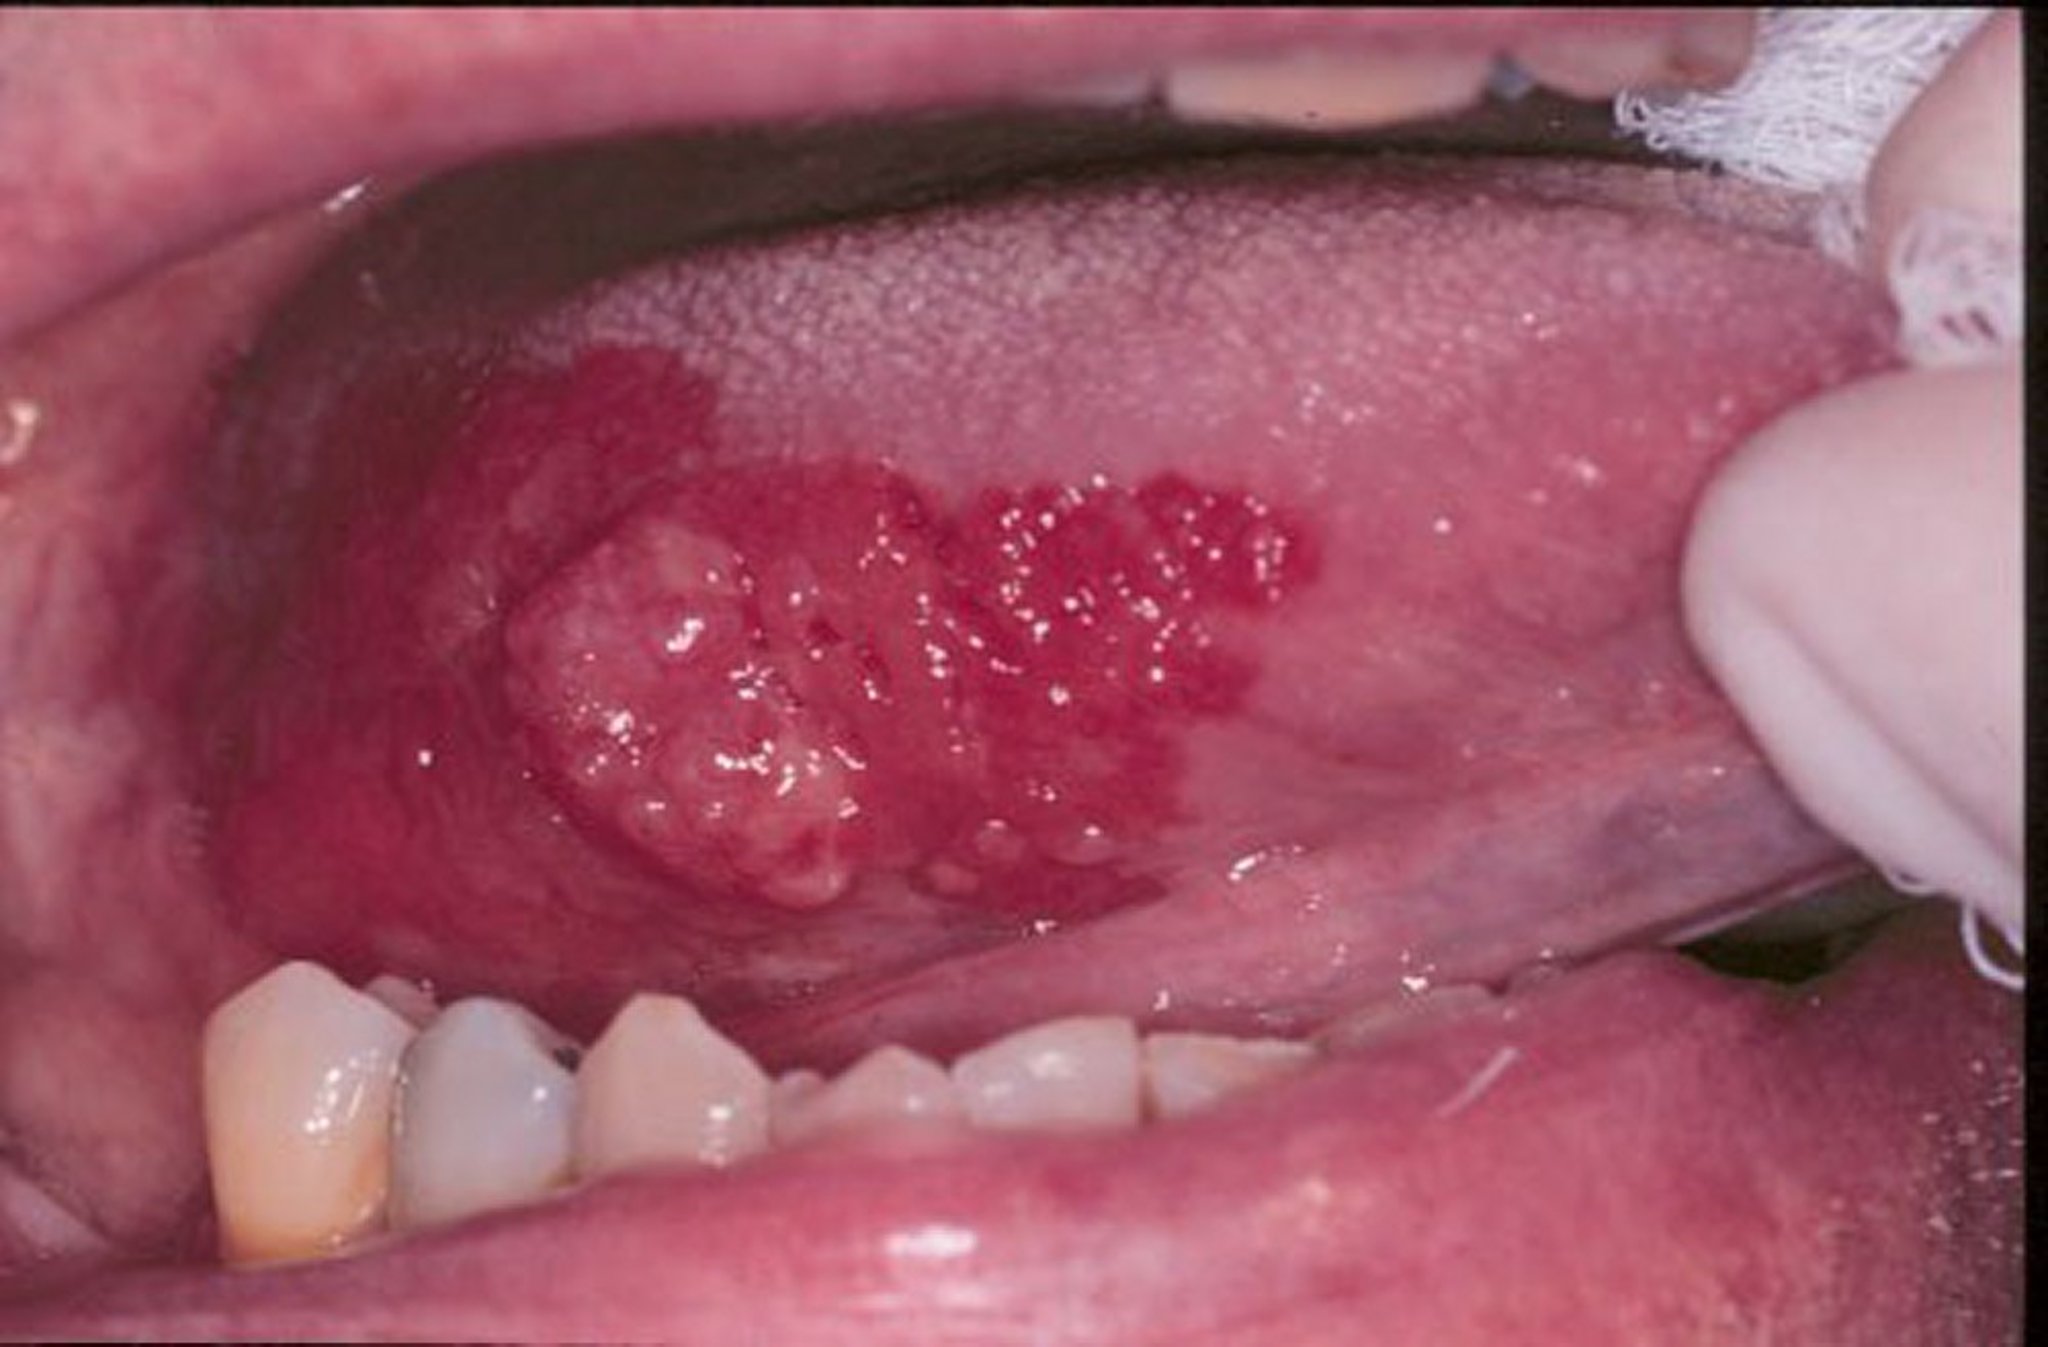

Erythroplakia and Squamous Cell Carcinoma

Erythroplakia is a general term for red, flat, or worn-away velvet-looking sores that develop in the mouth. In this image, a squamous cell carcinoma is surrounded by a margin of erythroplakia.

Image provided by Jonathan A. Ship, DMD.